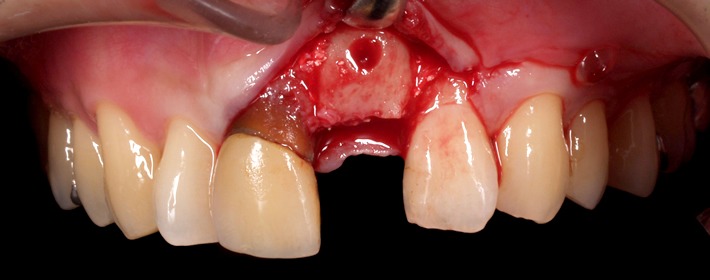

自家骨をブロックで採取して移植(ベニアグラフト)し、骨の厚みを増します。

最善の位置・角度でインプラント埋入